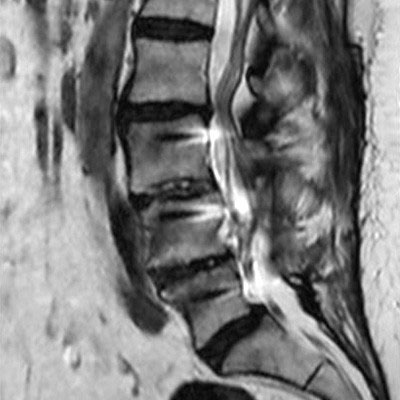

Lumbar Spine with metal implant, routine and fast

Utrecht Medical Center, The Netherlands

**Only for use with MR Safe or MR Conditional Implants by strictly following the Instructions for Use.